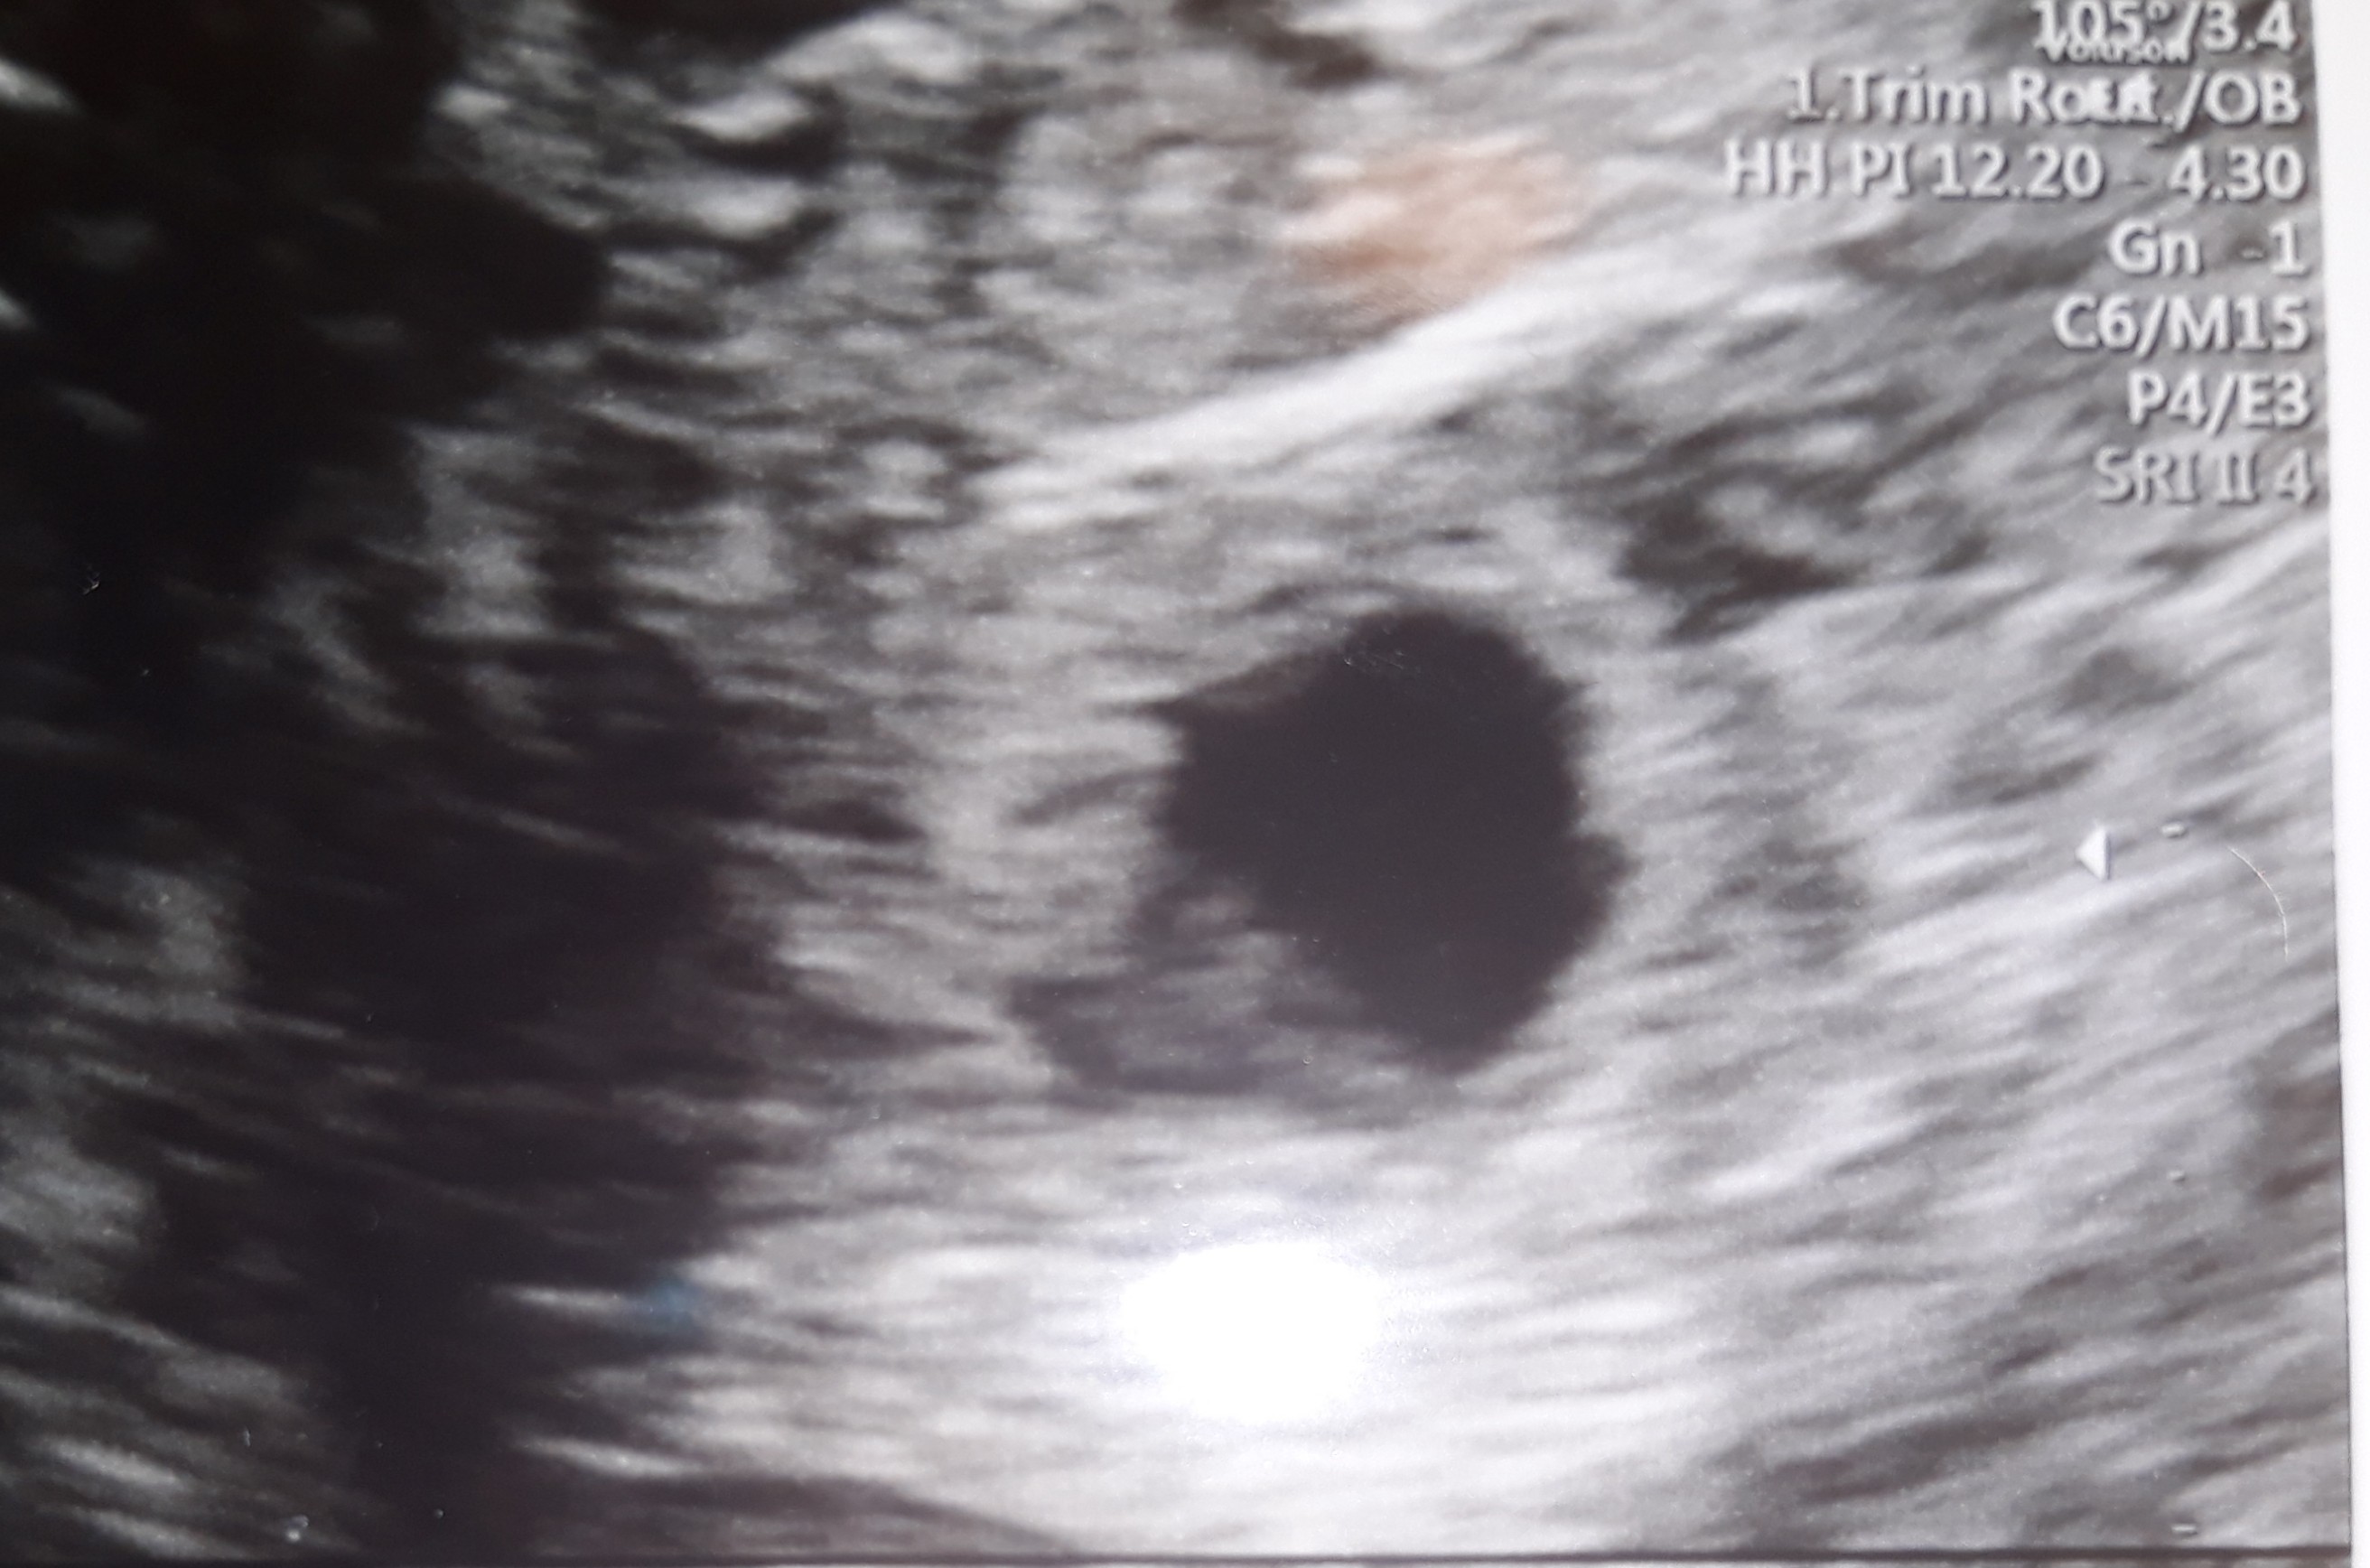

5 tydzień, nieregularny pecherzyk ciążowy

To moja 4 ciąża, poprzednie 3 straciłam. Teraz od razu od pozytywnego testu zaczęłam brać heparynę drobnoczasteczkową. Dokładnie w dniu spodziewane miesiączki miałam brązowe plamienie, jednorazowe, bez żadnego bólu. Do ginekologa poszłam w 5 tygodniu, na usg pęcherzyk uwidoczniony w macicy, ale... jego kształt jest nieregularny. Brzegi nie są równiutkie, nie jest to idealne kółko. Miałam zrobić bete w odstępie 48 godzin, pierwsza już za mną 7140, więc 5-6 tydzień.

To są zdjęcia mojego nieregularnego pęcherzyka.

• 20210417_113618.jpg

20210417_113618.jpg

582,8 KB · Wyświetleń: 915